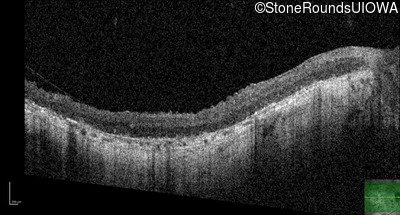

Age at visit: 33 years